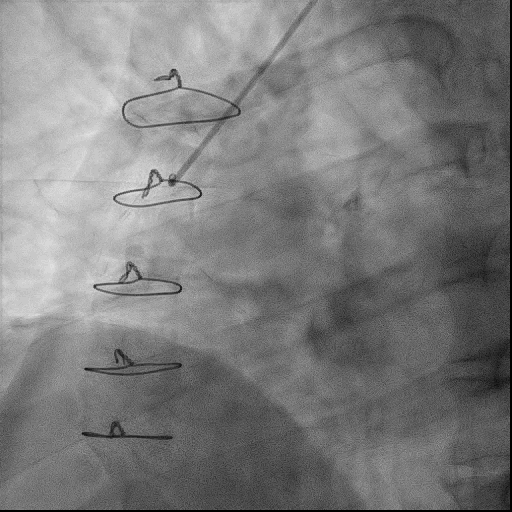

术前冠脉造影

RCA自近端齐头闭塞,无残端,远端隐约可见自身侧支形成,后三叉显影不佳

左侧LIMA-LAD、SVG-OM1桥血管通畅

右侧SVG-RCA桥血管闭塞